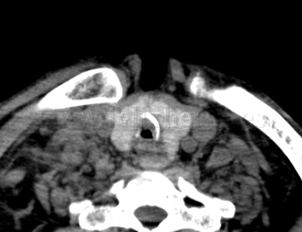

Estenosis traqueal post traqueotomía